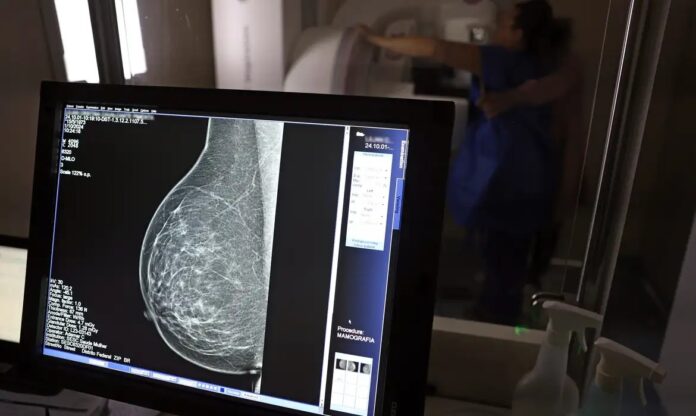

A Prefeitura de Ribeirão Preto lança a campanha do Outubro Rosa 2025, com foco no rastreamento e no diagnóstico precoce do câncer de mama. O grande destaque da ação é a abertura de 1.200 vagas extras para mamografias, que podem ser agendadas de forma simples e rápida pelo site da Prefeitura, no link: https://www.ribeiraopreto.sp.gov.br/portal/saude/.

As vagas são destinadas a mulheres e homens trans de 40 a 74 anos, que não apresentem queixas clínicas e tenham realizado o último exame há mais de dois anos. O agendamento garante a realização da mamografia de rastreamento em até três meses.

Em casos em que a paciente apresenta dor ou nódulos, o exame deve ser solicitado diretamente na unidade de saúde de referência, com prioridade no agendamento do diagnóstico.

No ano passado, Ribeirão Preto realizou 14.693 exames de mamografia na faixa etária de 40 a 74 anos. Já em 2025, até julho, foram feitas 9.635 mamografias de rastreamento em mulheres de 40 a 74 anos.

Segundo a pasta, a expectativa é que a ampliação das vagas, somada às ações de conscientização, aumente o acesso da população ao exame e contribua para a detecção precoce do câncer de mama.